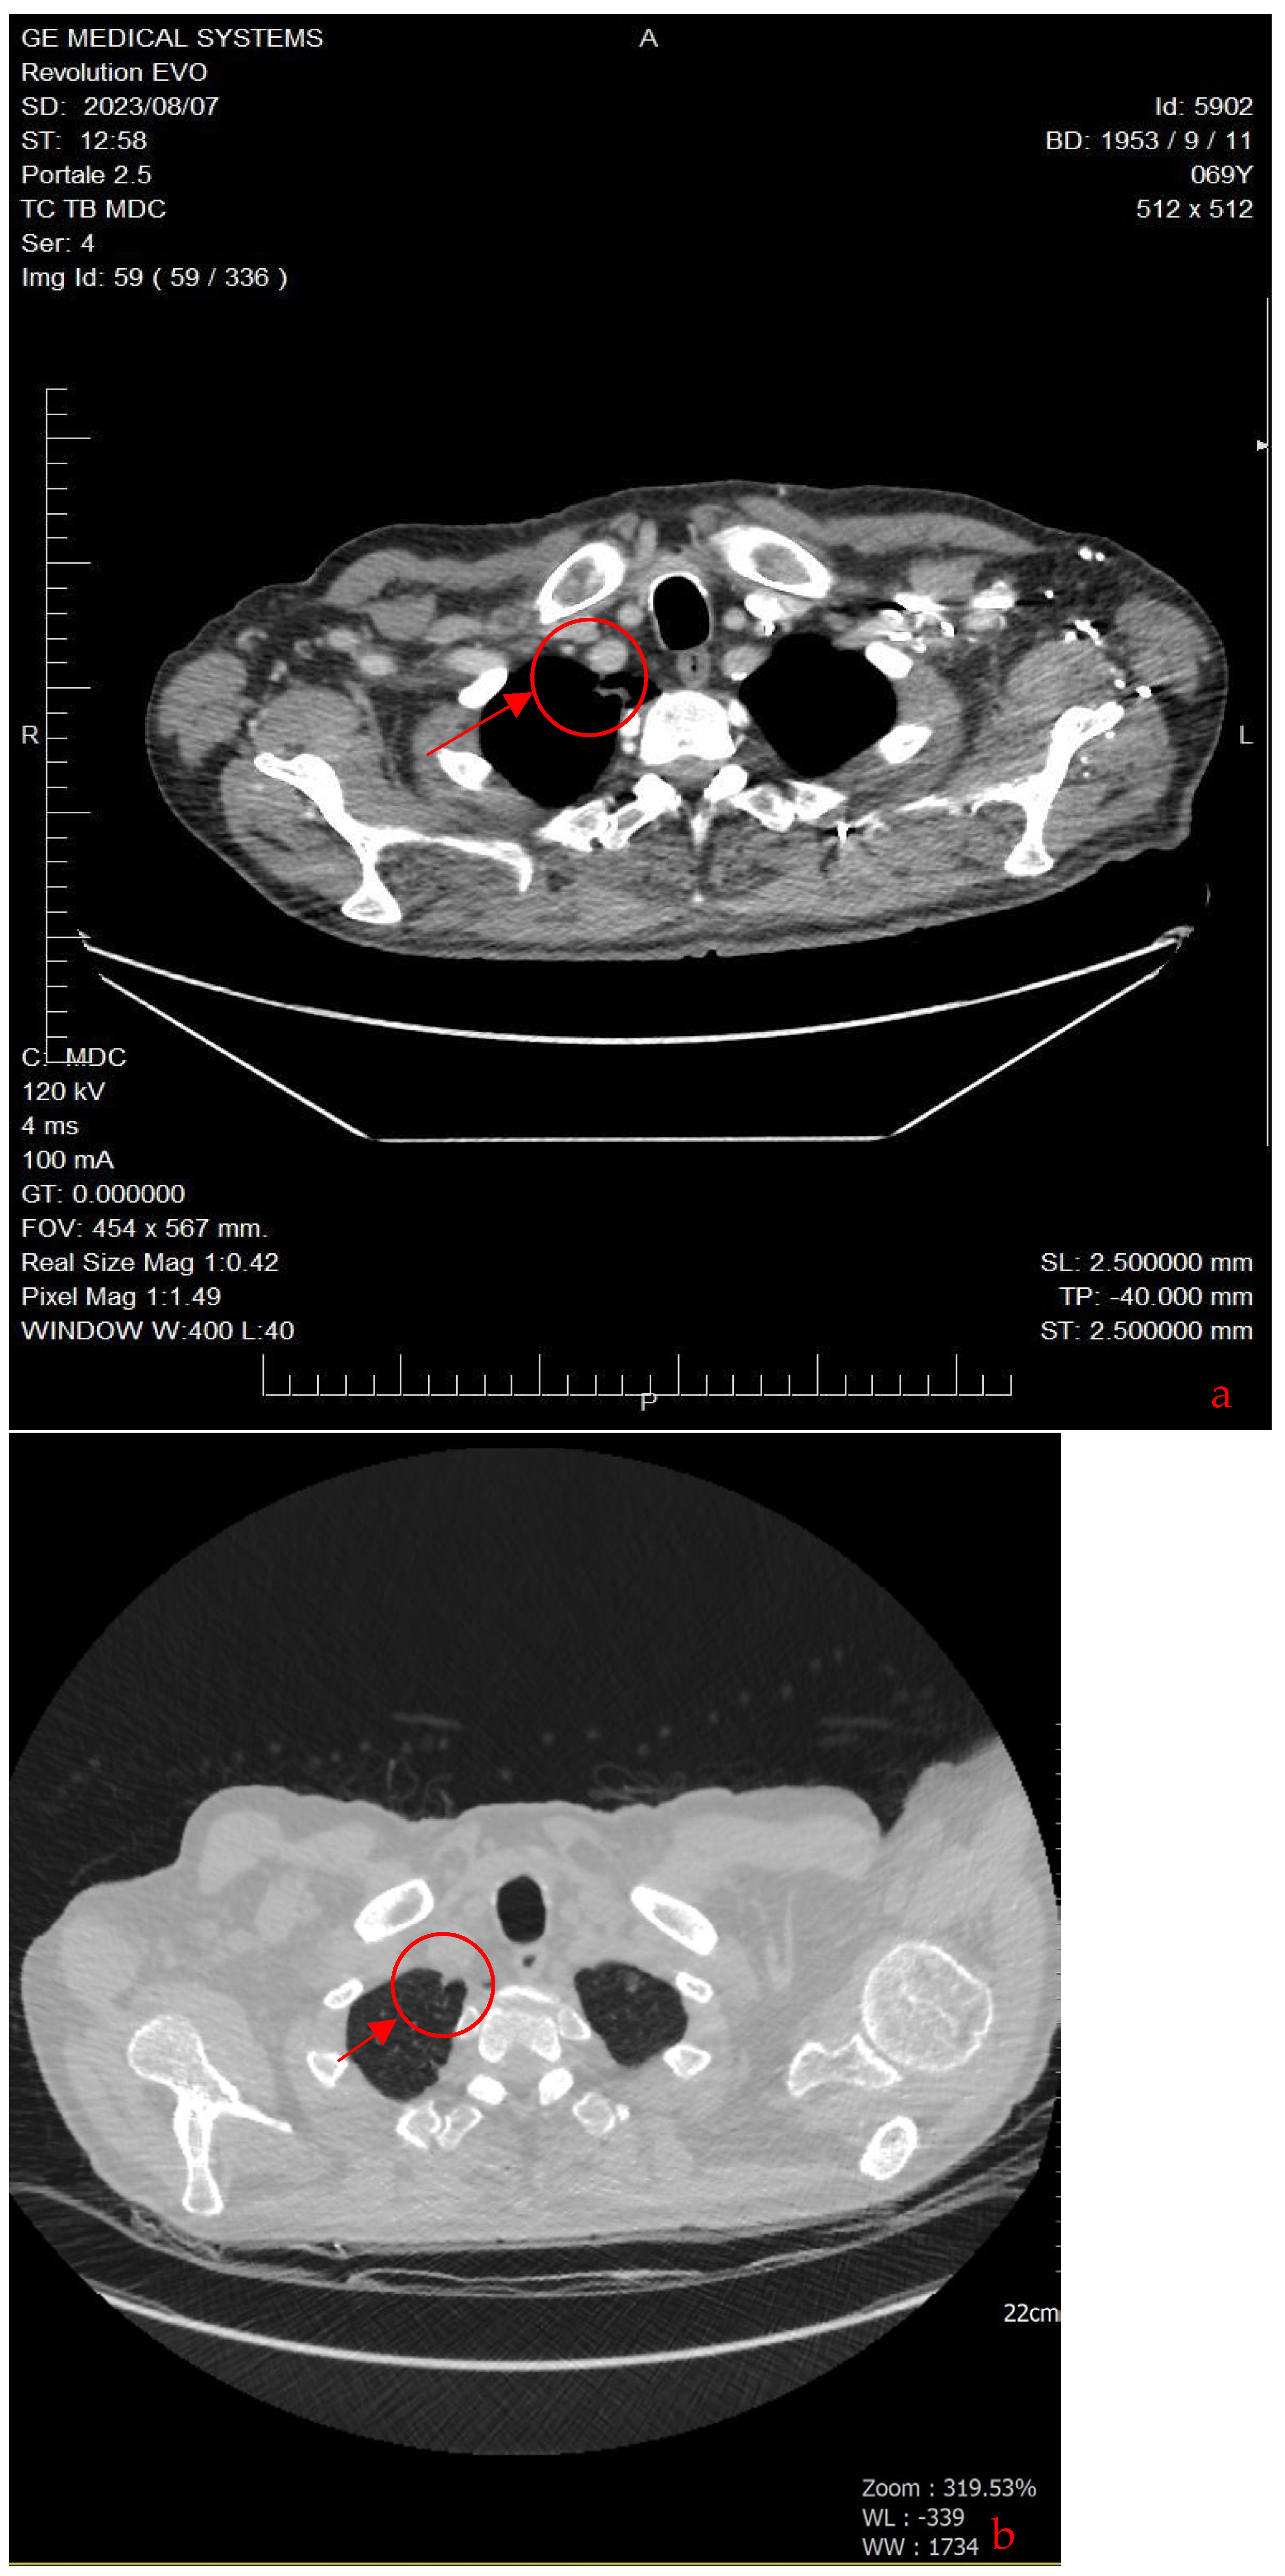

| 2023 | Latest total body CT scan | No evidence of neoplastic disease detected. |